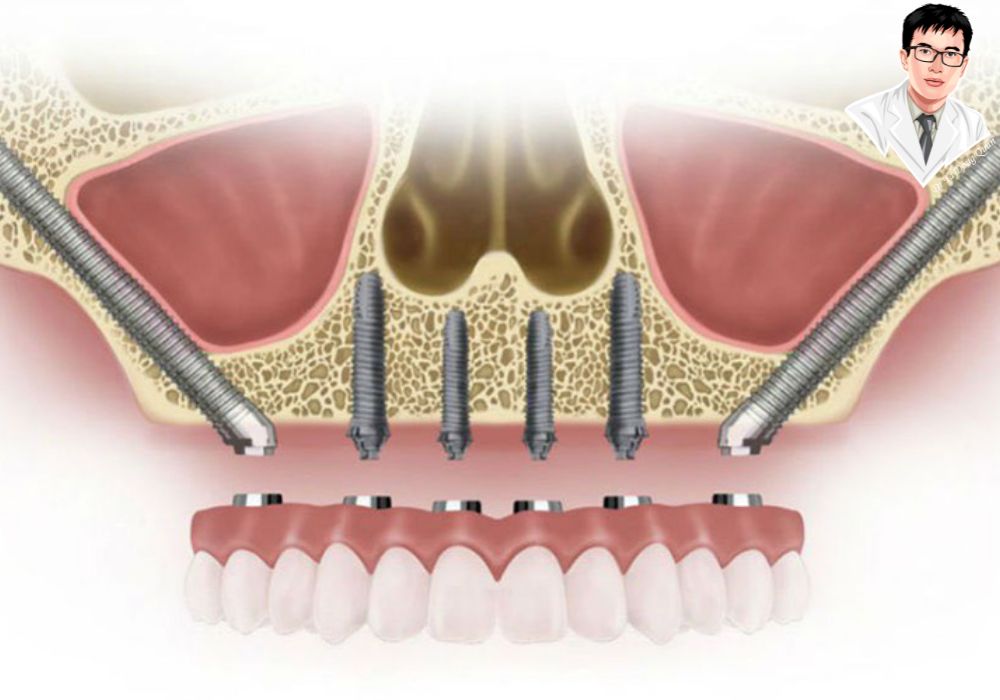

Implant xương gò má là trụ titanium dài, được đặt vào xương gò má – nơi chắc khỏe hơn xương hàm đã tiêu. Trụ này giúp nâng đỡ răng giả cố định, thay thế cho cả hàm trên nếu cần, mà không cần nâng xoang hay ghép xương.

Với người mất răng lâu năm và tiêu xương nặng, việc trồng răng luôn là một thử thách vì không còn đủ nền xương hàm để đặt trụ. Implant thường hoặc All-on-4 thường thất bại trong những trường hợp này. Tuy nhiên, implant xương gò má được thiết kế đặc biệt để khắc phục điều đó: trụ dài được neo vào xương gò má – nơi có mật độ xương chắc khỏe nhất vùng mặt, giúp cố định chắc chắn mà không cần ghép xương hay nâng xoang.

So với All-on-4: Phạm vi ứng dụng rộng hơn

All-on-4 thường phù hợp khi bạn còn đủ xương hàm trước và có điều kiện xương tốt. Với người tiêu xương nghiêm trọng, phương pháp này trở nên kém hiệu quả. Implant xương gò má không phụ thuộc vào chất lượng xương hàm trên, có thể áp dụng cả trong trường hợp xương tiêu hết – đây là điều All-on-4 không làm được. Ngoài ra, implant xương gò má có tỷ lệ thành công cao hơn ở bệnh nhân lớn tuổi hoặc có bệnh lý nền.